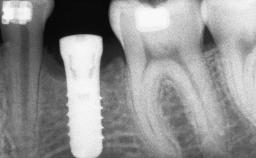

A 47-year-old woman who had suffered from aggressive periodontitis requiring a number of periodontal interventions over more than 10 years was referred by her general dental practitioner and periodontologist for bone augmentation and implant therapy. Her failing dentition had already been scheduled for extraction. The patient expressed a desire for implant-supported fixed restorations and esthetic improvement of her lower face. She had agreed to consult with a maxillofacial surgeon after the referring dentist had suggested bone augmentation. An initial examination by the maxillofacial surgeon revealed mobility of all residual teeth in a patient who was very unhappy with the function of her removable partial dentures. Due to periodontally migrated flaring teeth and loss of occlusal support, the vertical dimension of occlusion was dramatically reduced. The patient was displeased with her lower face because of deepened nasolabial, commissural, and supramental folds.